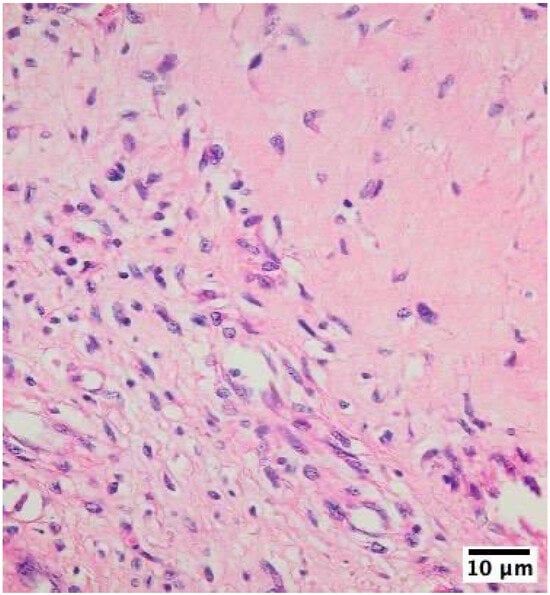

The inflammatory infiltrates in non-IE cases consisted mainly of macrophages and lymphocytes, suggesting a chronic inflammatory process rather than an acute infection (Figure 2, Figure 3 and Figure 4).

Figure 2. Histological examination of a mechanical heart valve tissue specimen in mitral position showed non-infective inflammatory degenerative lesions as visualized using hematoxylin–eosin staining at 400× magnification with an Olympus BX43 microscope and XC30 camera. This finding is characterized by the presence of numerous macrophages lining the area surrounding the mechanical valve. The accumulation of these immune cells suggests an ongoing inflammatory process, which may be a response to the presence of the artificial valve or a result of chronic tissue irritation.